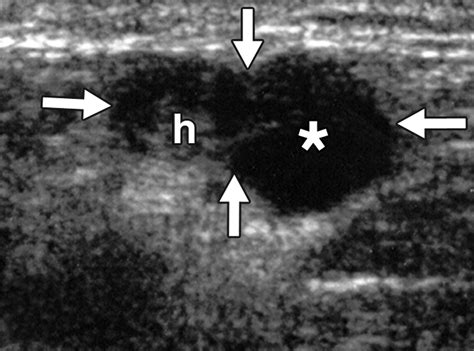

• Internal Architecture: Healthy nodes have a clear, bright central area called the “fatty hilum.” The absence of this hilum can be a warning sign.

• Blood Flow Patterns: Using Doppler technology, radiologists can assess how blood flows into the node. Abnormal vascularity is often a key marker for pathology.

• Border Definition: Clear, regular borders are generally reassuring, while irregular or “matted” borders may warrant biopsy.